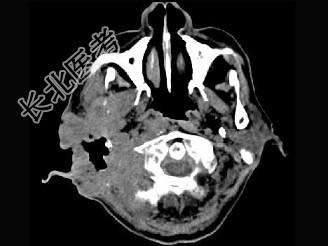

- 单项选择题男,56岁, 右侧腮腺疼痛肿胀半年,CT检查如图, 最可能的诊断是 ( )

A、右侧腮腺炎

B、右侧腮腺混合瘤

C、右侧腮腺癌

D、右侧腮腺转移瘤

E、右侧腮腺淋巴瘤